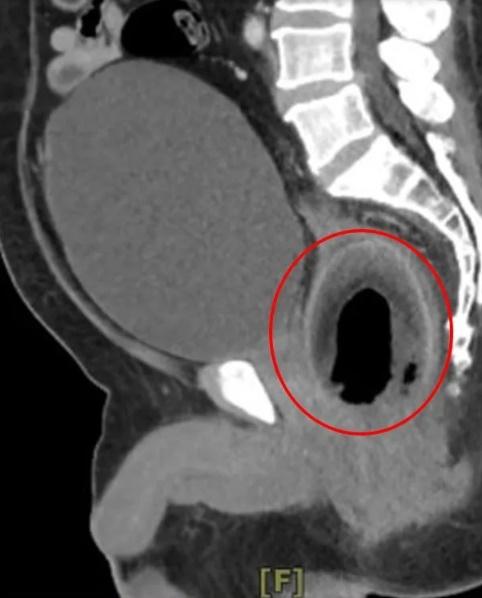

綜合報道,高雄義大醫院一般醫學外科主任、大腸直腸科主治醫生陳致一坦言,這是第一次碰到塞椰子的個案。他表示,男子是獨自求診,聲稱前一晚塞了東西入肛門裡,膀胱很漲,未能排尿,經電腦掃描(CT)發現,男子的膀胱漲到有如一個橄欖球,估計裡面大概有近2,000毫升的尿,幾漲爆,另外直腸也有個圓形異物,向男子查詢後,對方回答:「椰子」。醫護試過先為男子導尿,但被椰子卡住,尿管插不入膀胱,再試過用手及多種器械,伸進去男子肛門,但無論怎麼夾、怎麼挖,椰子仍是原封不動。經過評估,倘若繼續拖延下去,恐會膀胱爆破、直腸壞死,陳致一立即進行手術,以類似「剖腹產」的方式,剖開直腸取出椰子。但到底如何將椰子塞入肛門,男子直至出院仍不願透露。

陳致一指,肛門塞異物最可能的危險,就是造成肛門撕裂傷,恐留下括約肌鬆弛、滲便的後遺症,再者異物也可能傷害直腸組織,可能被塞傷、塞破,而上述男子所塞的椰子,更是卡住膀胱出口,還有膀胱漲破的風險,奉勸有此習慣者,還是不要「逆其道而行」,以免後悔莫及。網上圖片顯示,那個取出的椰子的長度有約10厘米。